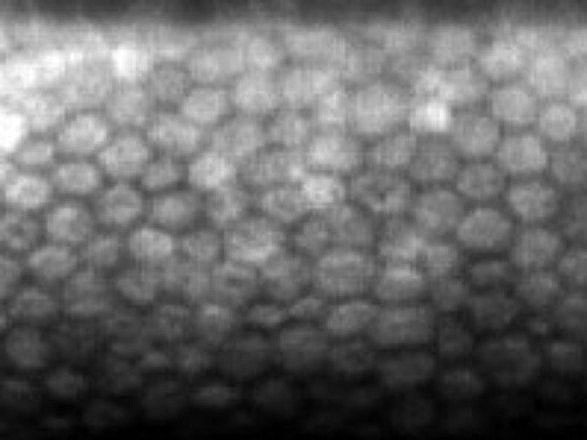

細胞がきれいな六角形を保ち、きちんと整列しています。(角膜内皮細胞解析装置による画像)